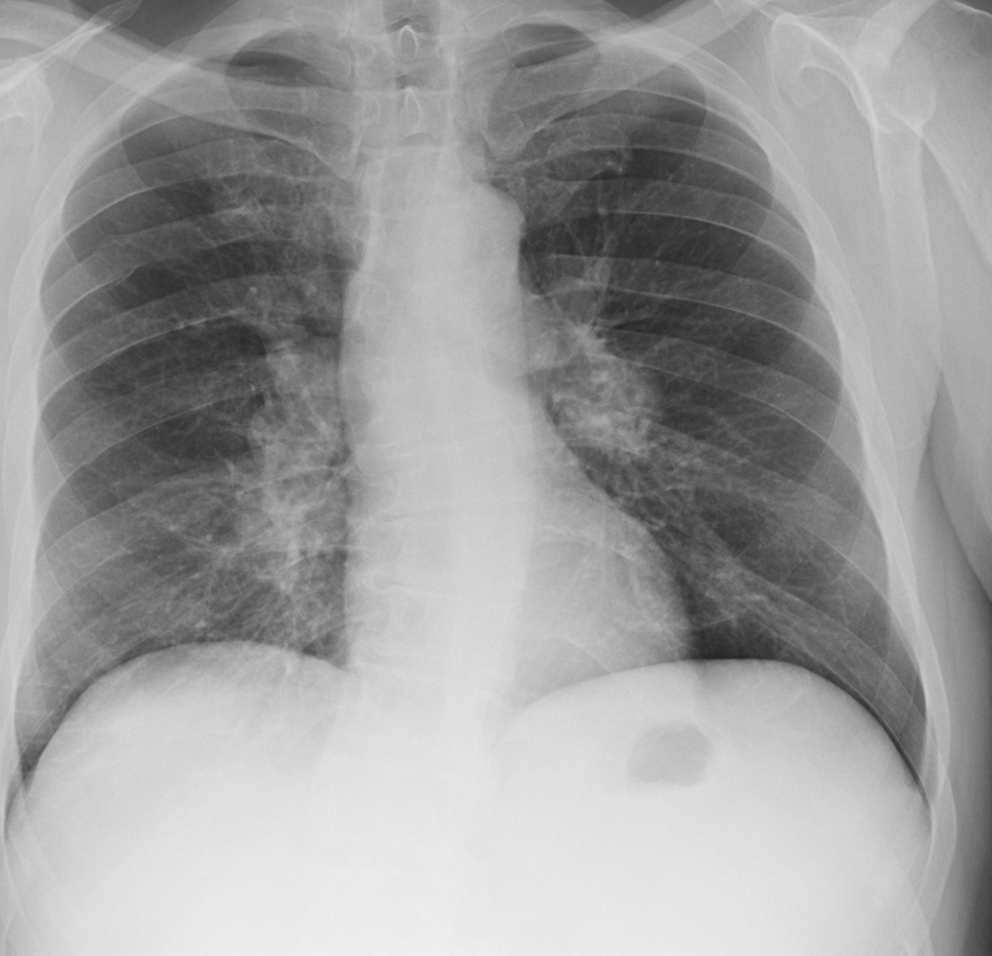

Mediastinum

Lymphoma

Lymphoma Nodes and splenomegaly